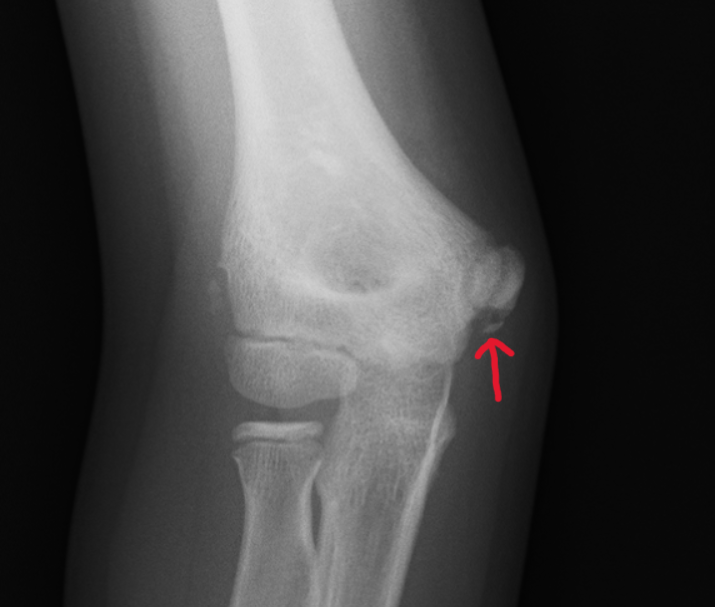

【右野球肘(〜内側上顆剥離骨折~)】

下の画像において右肘・左肘の順です。赤矢印がある右肘の内側の骨が剥がれているのが確認できます。